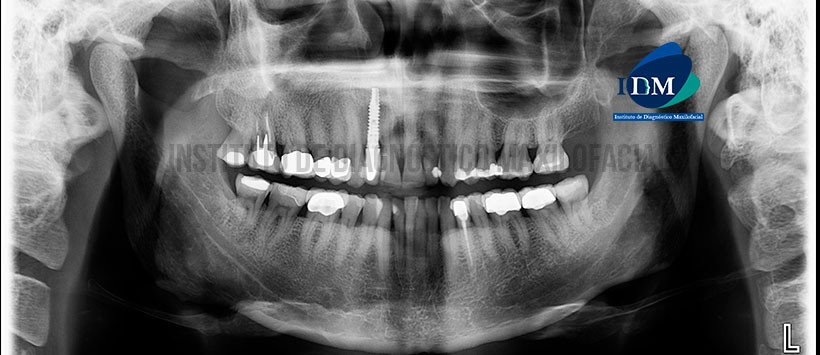

A la evaluación de la radiografía panorámica (Figura 1) se aprecia disminución de las dimensiones y opacificación del seno maxilar derecho en comparación a su contralateral. Aumento de la densidad ósea en zona alveolar de pieza 18, 17, 16.

A la evaluación de la tomografía volumétrica en cortes axiales (Figura 2), transaxiales (Figura 3) y tangenciales (Figura 4) se aprecia contenido isodenso con engrosamiento y aumento de densidad del piso, pared medial y lateral  del seno maxilar derecho. Se aprecia imágenes hiperdensas de densidad cálcica forma irregular localizados en el antro sinusal. Pieza 1.7 corona protésica, espigo en raíz distovestibular y obturación de conductos radiculares, se aprecia adelgazamiento de la pared distal del tercio medio cervical de raíz mesiovestibular con presencia de imagen hipodensa que se extiende hacia la zona de furca asociado a proceso osteolítico en furca y a nivel periapical, aumento de la densidad posea circundante que se extiende hacia la zona sinusal.

En las reconstrucciones 3D (Figura 5 y 6) se muestran de manera gráfica el proceso osteolítico de pieza 17, y el contenido del seno maxilar derecho con engrosamiento y aumento de la densidad ósea circundante.